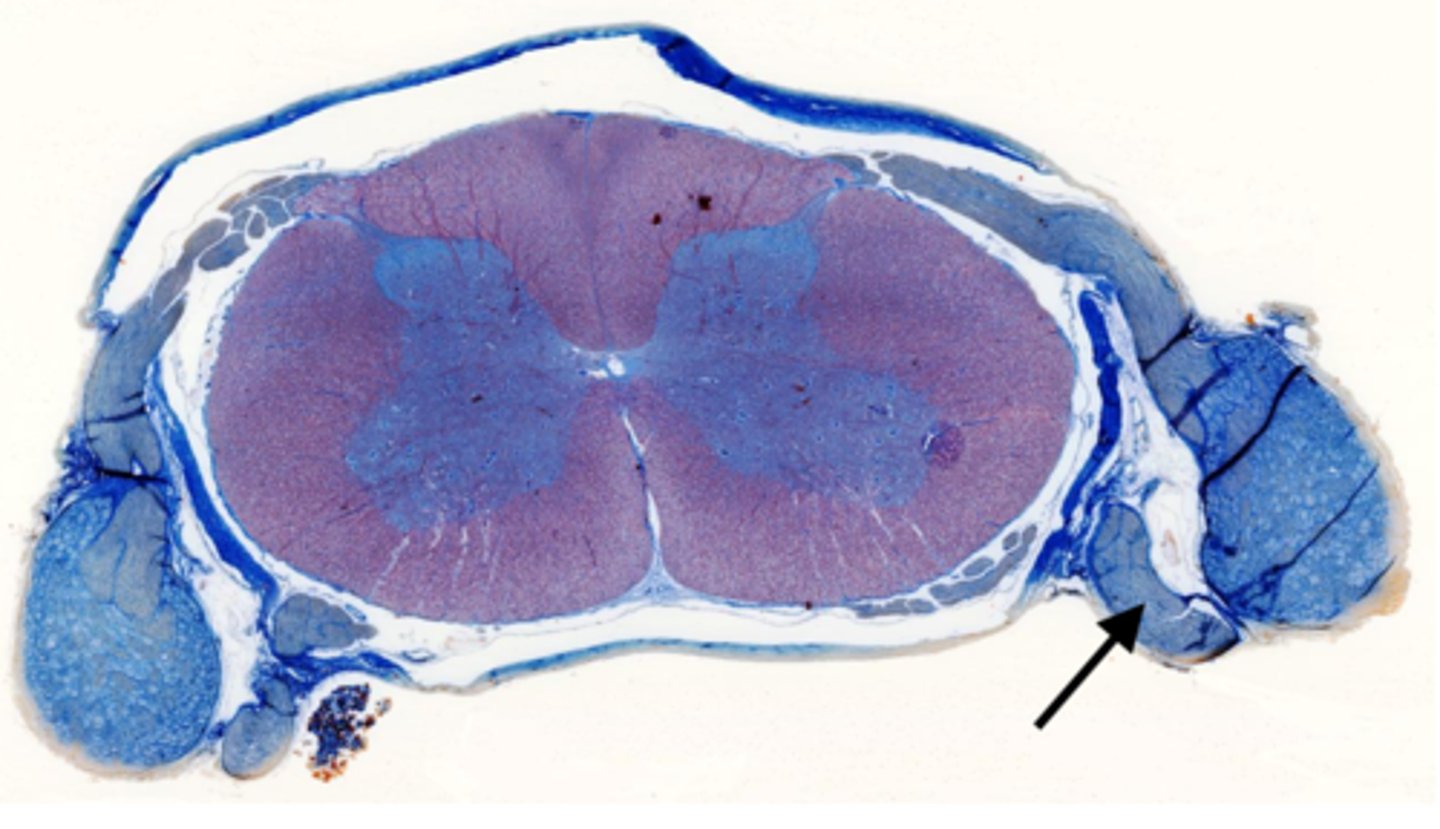

Identify the part of the spinal cord

dorsal funiculi

lateral funiculi

ventral funiculi

dorsal horn

ventral horn

dorsal root of spinal nerve

ventral root of spinal nerve

Identify the section of the spinal cord that contains nuclei

gray matter

Identify the section of the spinal cord that contains nerve tracts

white matter

central canal

Identify the part of the meninges

pia mater

arachnoid

dura mater

dorsal root ganglion